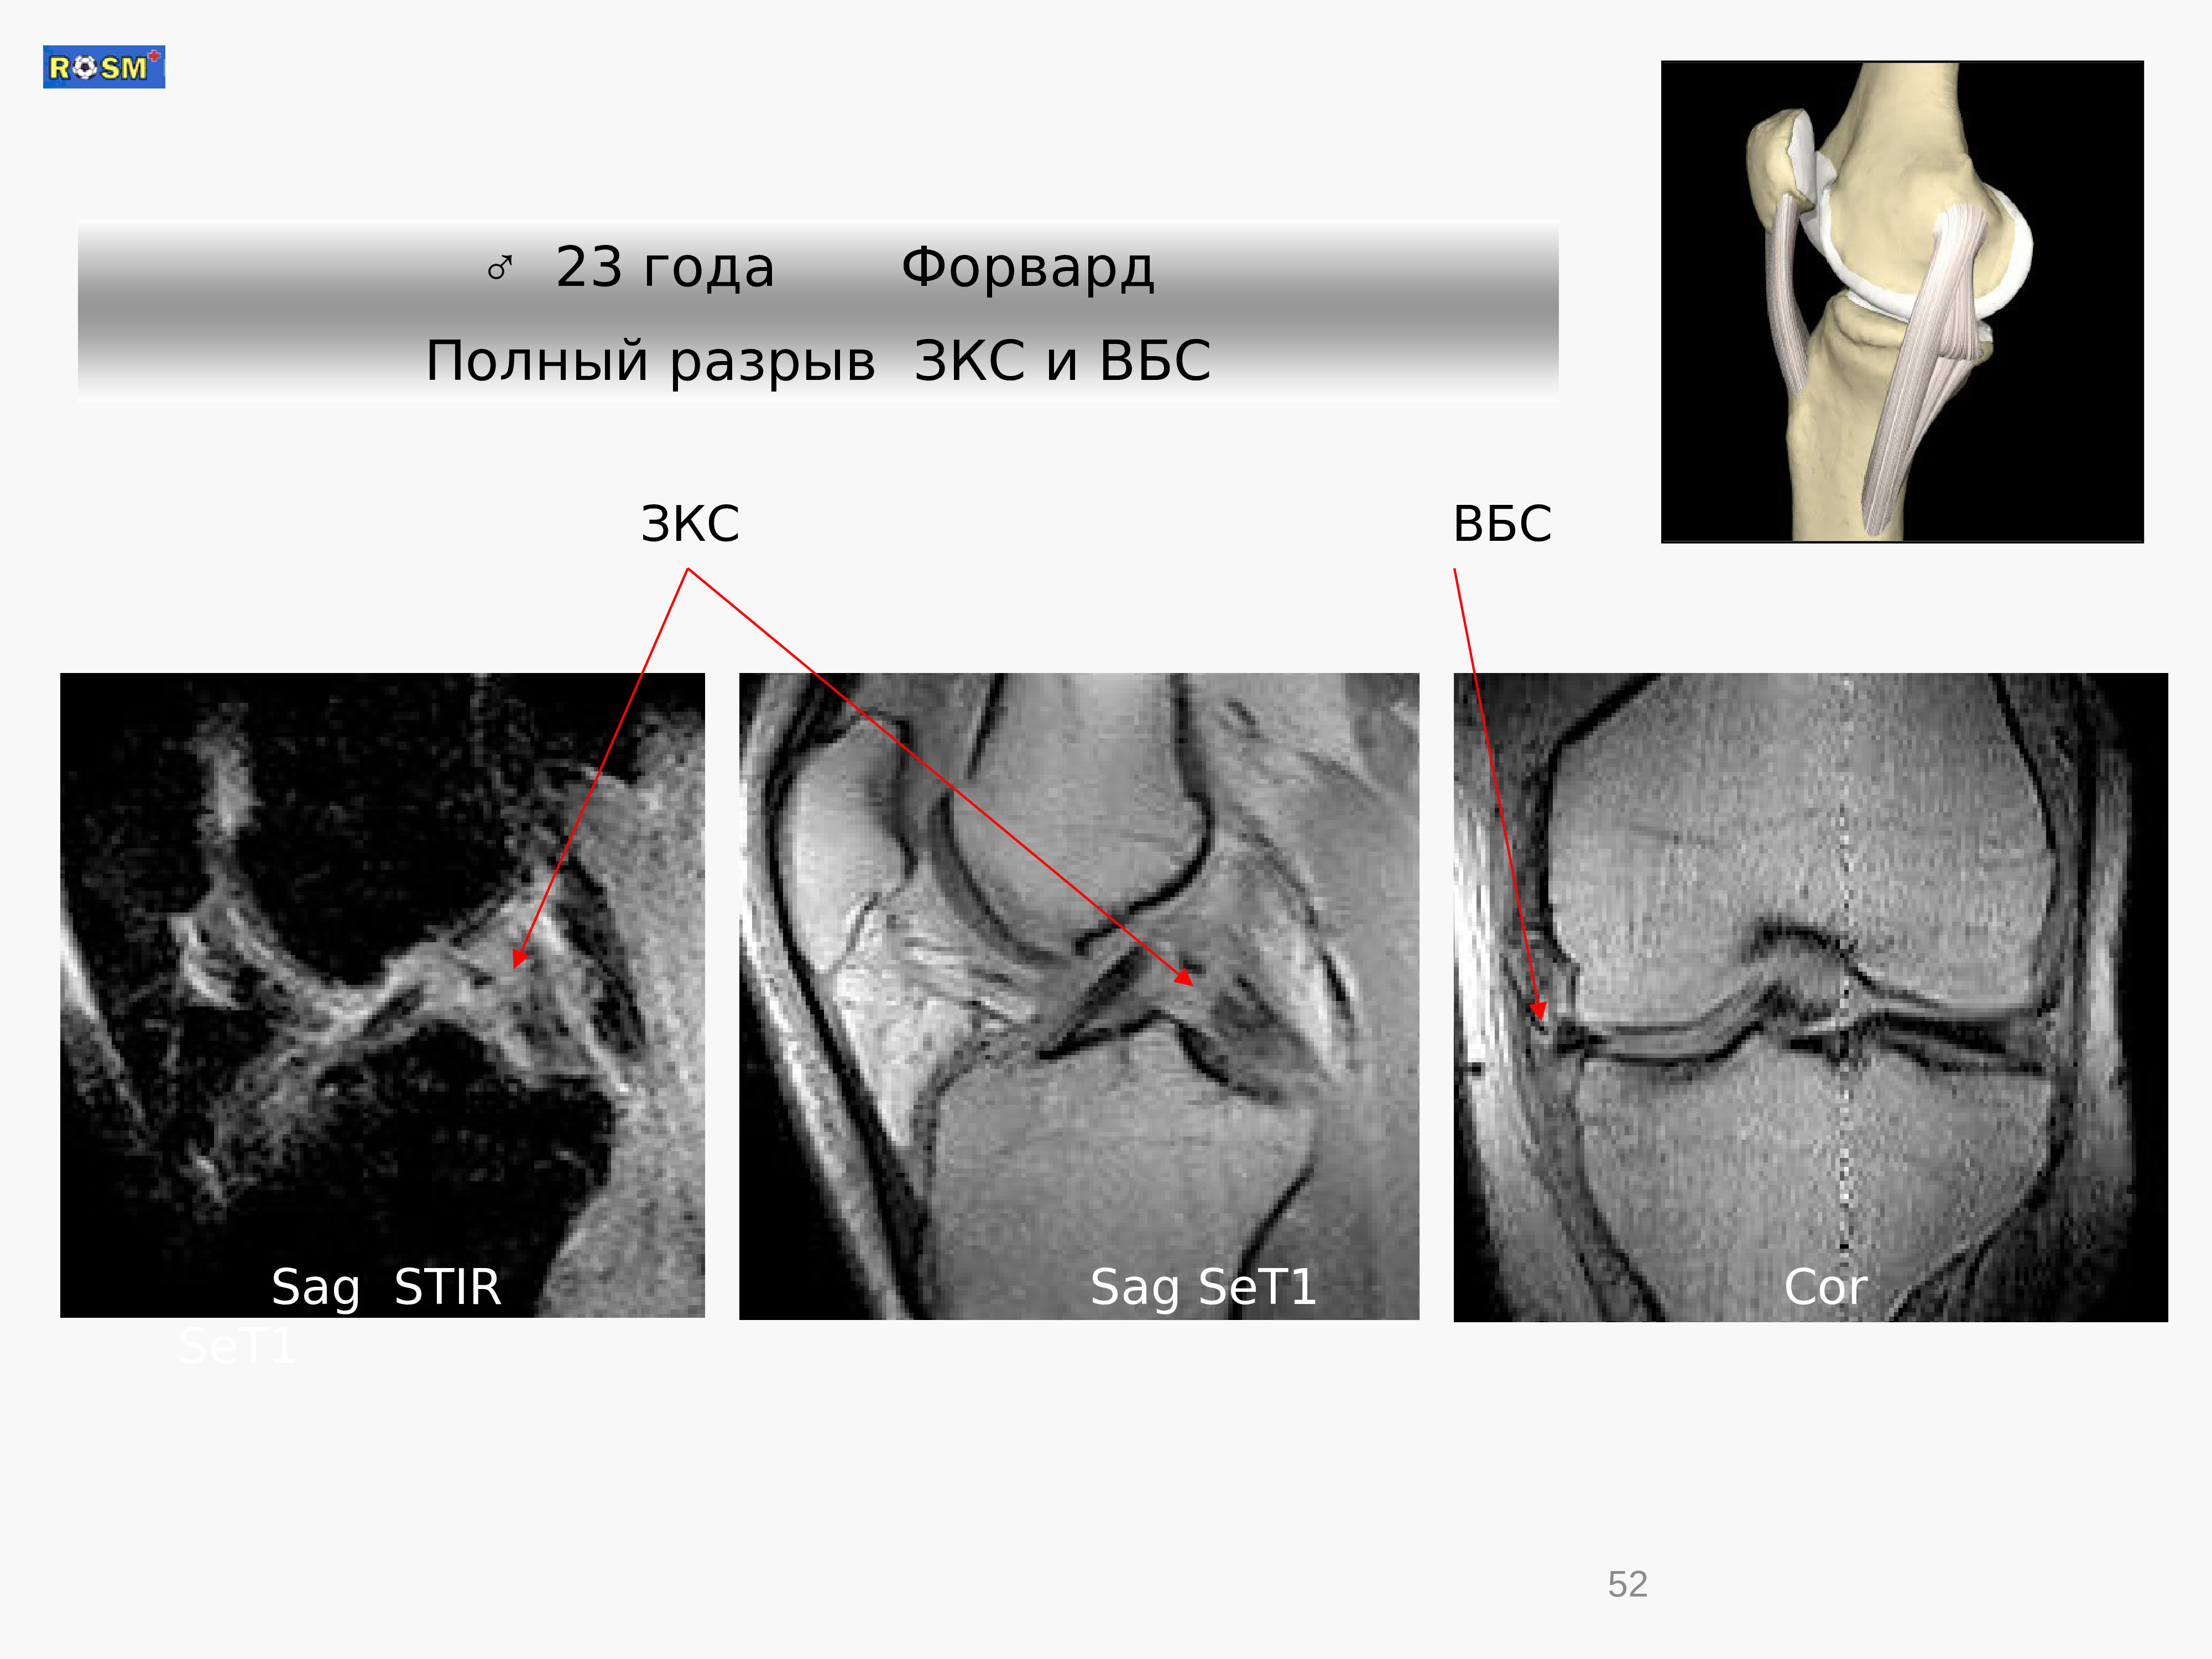

Полный разрыв рога 120 фотографий